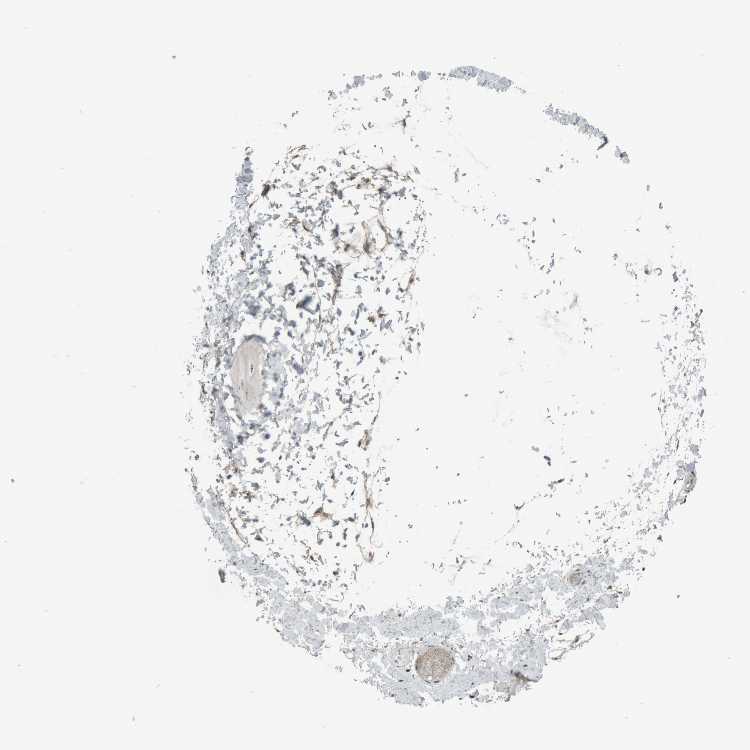

SOFT TISSUE 1 - Antibody stainingi

Antibody staining in the annotated cell types in the current human tissue is reported as not detected, low, medium, or high, based on conventional immunohistochemistry profiling in selected tissues. This score is based on the combination of the staining intensity and fraction of stained cells.

Each image is clickable and will lead to virtual microscopy that enables deeper exploration of all samples and also displays staining intensity scores, fraction scores and subcellular localization as well as patient and tissue information for each sample.

Antibody HPA024642

Chondrocytes Not detected

Fibroblasts Low

Peripheral nerve Not detected